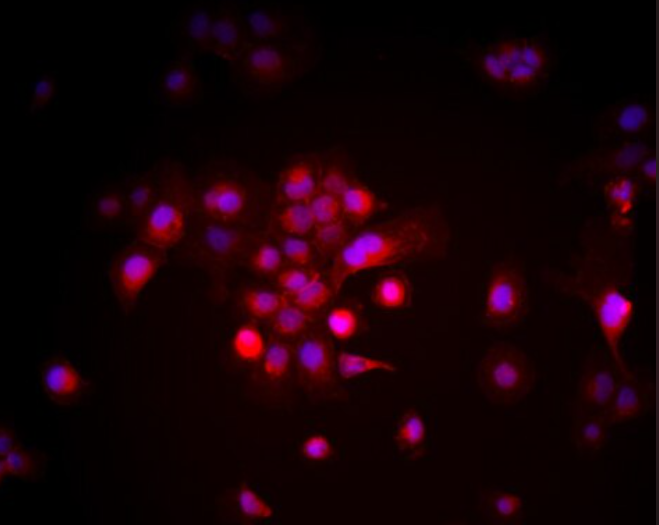

人高分化脂肪肉瘤细胞93T449(93T449细胞)来源于人脂肪肉瘤组织,是一种常用于脂肪肉瘤研究的细胞系。93T449细胞具有脂肪肉瘤的特征,能够表达脂肪相关标志物,在肿瘤研究中发挥着重要作用。作为脂肪肉瘤的高分化模型,93T449细胞能够模拟脂肪肉瘤的发生和发展过程,广泛应用于脂肪肉瘤的治疗和药物筛选研究中。